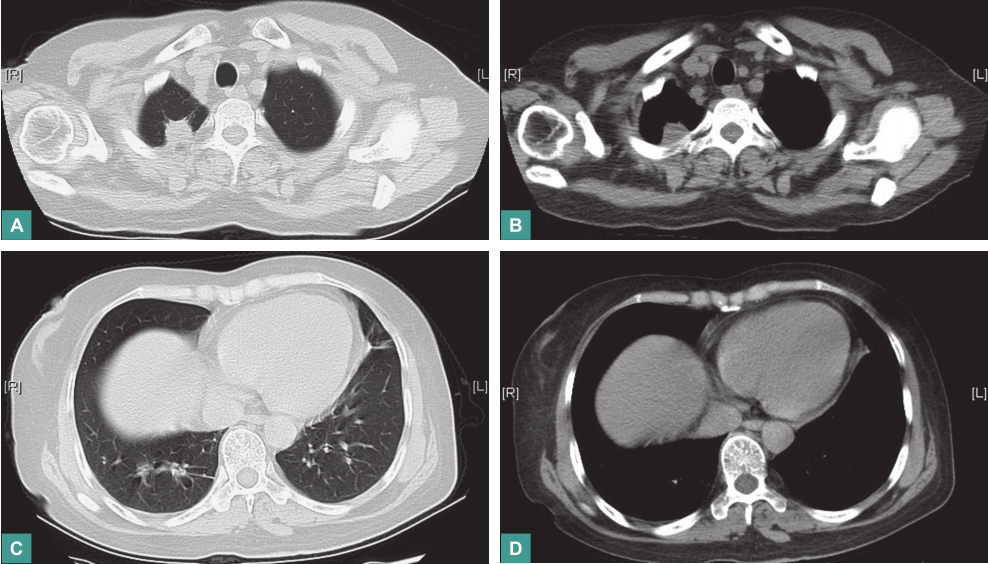

第二次冲击治疗后复查:

血沉23mm/h,C反应蛋白8.94mg/L。胸部CT:右肺上叶尖段占位病变较前明显缩小,双侧肺门区及周围多发结节状密度增浓影较前有所缩小,纵隔内多发小淋巴结较前有所缩小(图8)。

图8 第二次冲击治疗后复查胸部CT表现